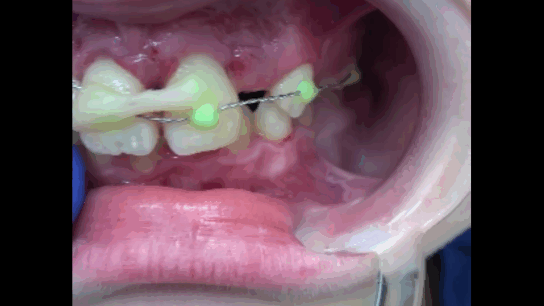

Распатором проведено аккуратное отслаивание слизисто-надкостничного лоскута, по возможности избегая касания корней зуба для максимального сохранения оставшихся периодонтальных волокон и клеток на поверхности корней зубов (Рисунок 10).

Рисунок 10. Отслоен слизисто-надкостничный лоскут. Признаки отсутствия костной ткани в апроксимальных участках и на вестибулярной поверхности корней зубов 1.1 и 2.1 на протяжении более чем 23 длины корней.

Визуализированы и удалены 2 эластических кольца из области апикальной трети зубов 1.1, 2.1 путем захвата кольца иглодержателем и рассечения ножницами, антисептическая обработка 0.05% раствором Хлоргексидина. Гнойного отделяемого не обнаружено, открытый кюретаж не проводился (Рисунки 11, 12).

Рисунок 11. Визуализированы и удалены два эластических кольца из апикальной трети пародонта зубов 1.1, 2.1.